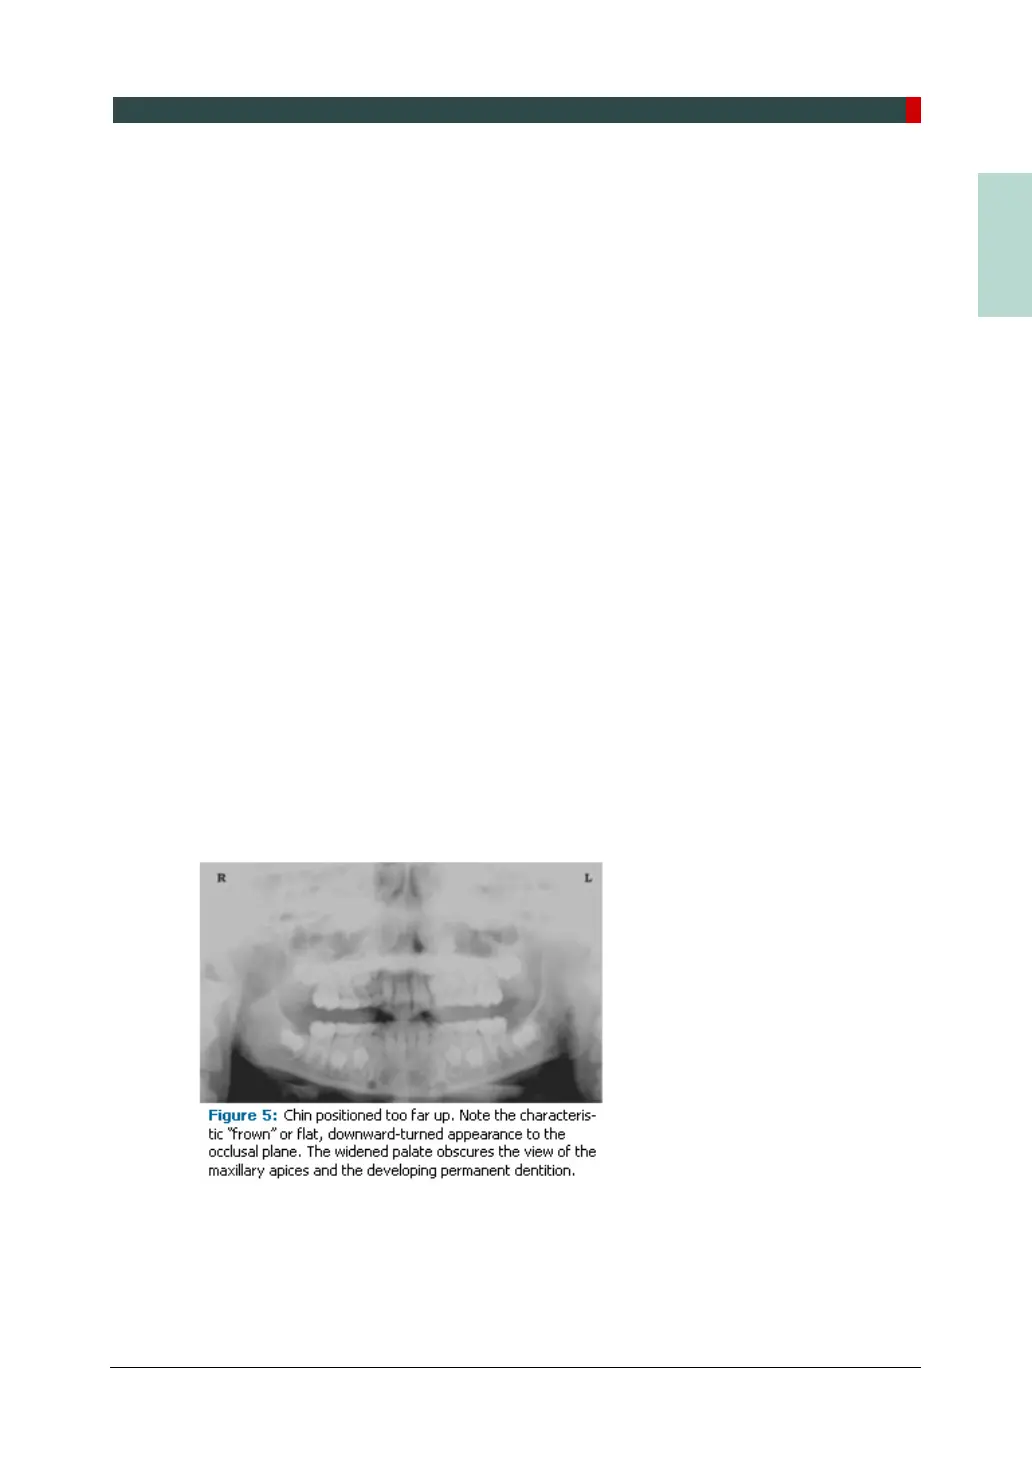

Superior-Inferior (Up-Down) Positioning Error

Positioning the dental arches within the superior-inferior (up-down) dimension of the focal

trough can be difficult to achieve, especially with children whose smaller size reduces the

distance between the shoulders and the inferior border of the chin. When the arches are

positioned incorrectly in the superior-inferior direction, the image exhibits multiple

distortions, including increased overlapping in the premolar regions. When the arches are

positioned too far up or down, the teeth will simultaneously move into a position that is too

far back or too far forward, respectively, out of the focal trough.

Positioning the arches too far superiorly produces a characteristic "frown" or flat,

downward- turned appearance to the occlusal plane (Figure 5). The condyles flare out

and off the edges of the image, and the palate appears as a widened, thick, dense

radiopacity. This positioning error results in a widened appearance of the palate and

obliterates the apical regions of the maxillary teeth, compromising the images of the

unerupted developing dentition. As the maxillary arch tips upward, the anterior teeth tilt

backward producing the same widened appearance that results from an incorrect anterior-

posterior position. Positioning the arches too far inferior produces a characteristic "smile"